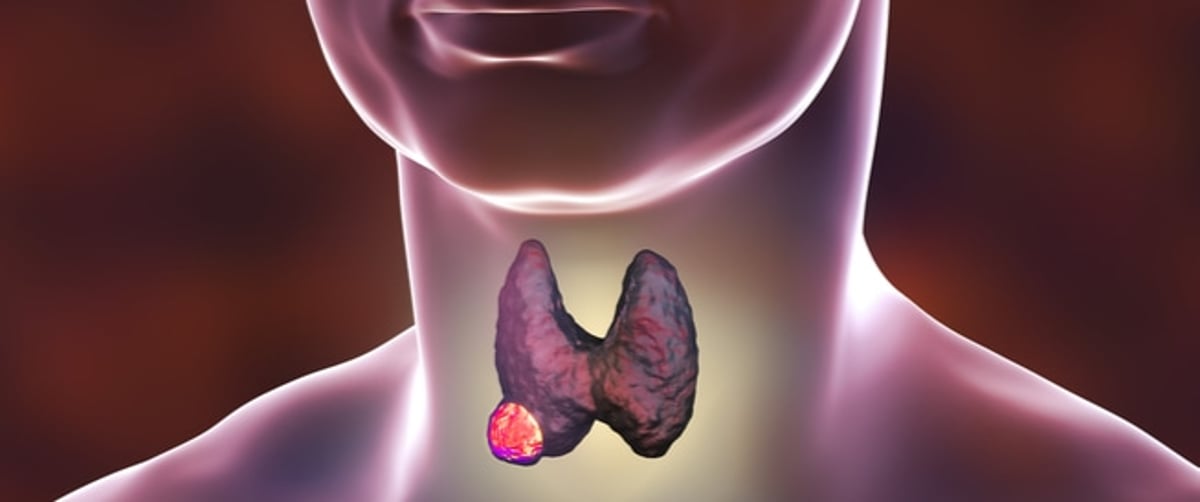

وتساعد الغدة الدرقية، التي تقع في الجزء السفلي من الرقبة، أسفل الحنجرة وفوق القصبة الهوائية، الجسم عن طريق إنتاج وإطلاق الهرمونات التي يمكن أن تساعد على الهضم وصحة القلب والعضلات.

وتفرز الغدة الدرقية ثلاثة هرمونات منفصلة: ثلاثي يودوثيرونين – المعروف باسم T3، وثيروكسين – المعروف باسم T4، والكالسيتونين.

وتتعدّد أنواع سرطان الغدة الدرقية، منها سرطان الغدة الدرقية الحليمي، والجريبي، والخلايا الورمية (خلايا هورثل)، إضافة إلى سرطان الغدة الدرقية النخاعي والكشمي.